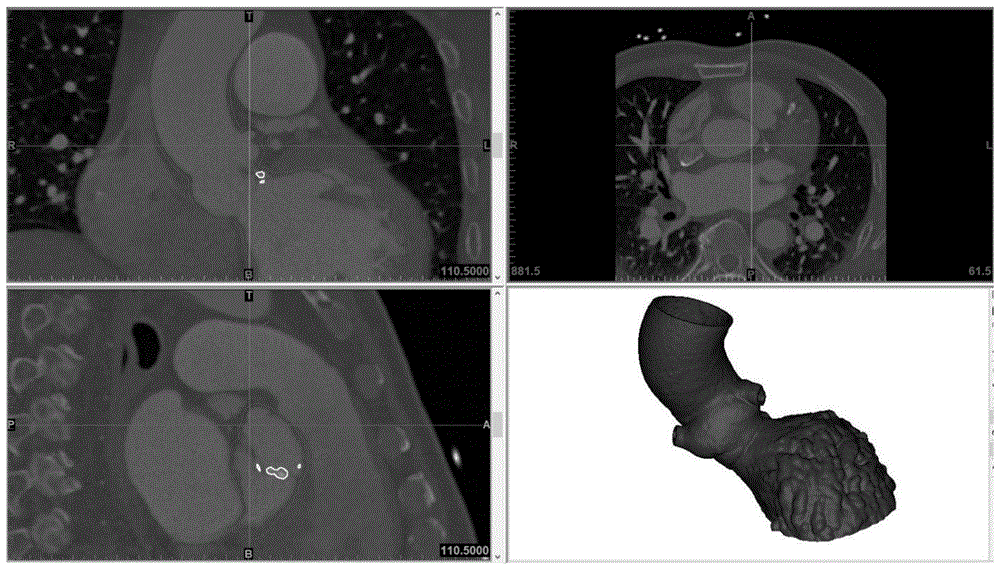

一种利用超声波原始数据引导制作心脏局部3D打印模型的方法